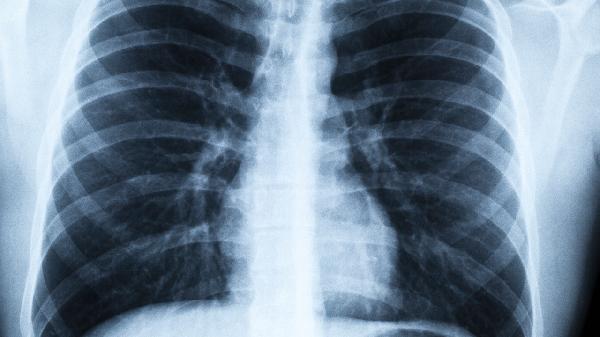

保护肺部健康需要从生活细节入手。除了远离烟草,更要警惕这些容易被忽视的"隐形杀手"。建议每年进行一次低剂量螺旋CT检查,这是目前筛查早期肺癌最有效的方法。记住,预防永远比治疗更重要,今天开始就给自己的呼吸系统多一些关爱吧。